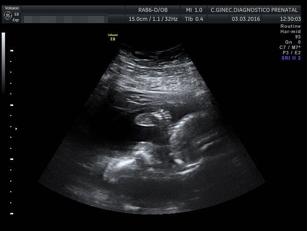

Pero las lágrimas acuden a tus ojos y tu corazón se llena de agradecimiento a Dios cuando descubres que una vez más –perdón dos veces más- unas nuevas vidas se meten de rondón en la tuya. Patricia y Ana, las dos mozas de veintitantas semanas, nietas mías, la 15 y la 16, que he conocido hoy en su peso, medidas, vísceras, rasgos y hasta en su vesícula biliar, son dos nuevos seres completos, vivos y capaces de pelearse entre ellas.

Le he insistido al médico. ¿Son únicas e irrepetibles? ¿Son personas en todos los conceptos? El galeno ha corroborado lo que sentía mi corazón. Dos seres bajitos de veintitantos centímetros y 300 gramos de peso. Llenas de vida y de esperanza. Rodeadas de amor y de cuidados.